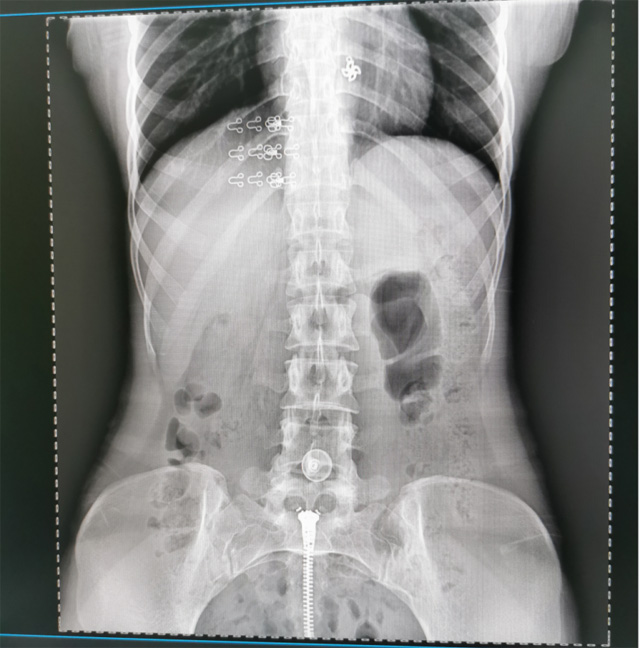

提高醫(yī)院的影像科的醫(yī)療服務(wù)水平,滿足滿足人民群眾不斷增長的醫(yī)療需求,促進醫(yī)療技術(shù)快速發(fā)展。醫(yī)院都引進懸吊DR拍片設(shè)備新一代數(shù)字化X線攝影系統(tǒng)。標志著醫(yī)院的診療水平又上升一個新的臺階。懸吊DR滿足人體頭部、胸部、腹部、腰椎、四肢等部位的數(shù)字攝影檢查,可以檢查呼吸系統(tǒng)疾病,心臟系統(tǒng)的疾病、骨關(guān)節(jié)系統(tǒng)的疾病,子宮輸卵管造影、胃腸道造影,.有職業(yè)病體檢篩查塵肺病功能。通過DR數(shù)字化攝影,分段連續(xù)、重疊采集數(shù)字化圖像,利用軟件對圖像進行拼接的方式來獲得全脊柱、全上肢或全下肢的圖像。新設(shè)備的圖像更清晰,臨床拍攝避免患者再次搬運和移動產(chǎn)生的痛苦,是創(chuàng)傷骨折患者的福音。輻射減少受照劑量50%,后處理能力強、圖像質(zhì)量高。有效降低操作難度,縮短工作流程,尤其適合大批量體檢。

具有射線劑量小、圖像清晰度高、誤差小等特點,懸吊DR已廣泛應(yīng)用于各級醫(yī)療機構(gòu)的體檢中心,越來越受到臨床醫(yī)生的肯定和患者的青睞。為臨床診斷工作提供更加直觀有效的技術(shù)支持,大大提高了患者就醫(yī)效率從而為患者提供更加優(yōu)質(zhì)的醫(yī)療服務(wù)。提高了其成像質(zhì)量和臨床應(yīng)用價值,并極大減少了受照輻射劑量。有效滿足了各種常見疾病的臨床診斷和治療需求。以醫(yī)療質(zhì)量為根本,以優(yōu)質(zhì)服務(wù)為導(dǎo)向,竭誠為人民群眾的健康保駕護航。